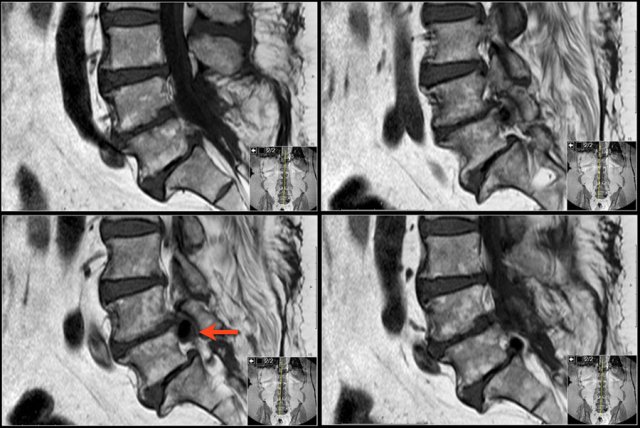

Use of a marker

When you notice an abnormality, it can be helpful to use a marker that correlates with the same location on the other series.

If you enlarge the image, you will see the small yellow cross, which indicates that you are looking at the exact same spot on the other series.

Here the L5 nerve on the right is compressed by a synovial cyst, which is the result of facet arthrosis with effusion within the intervertebral joints.